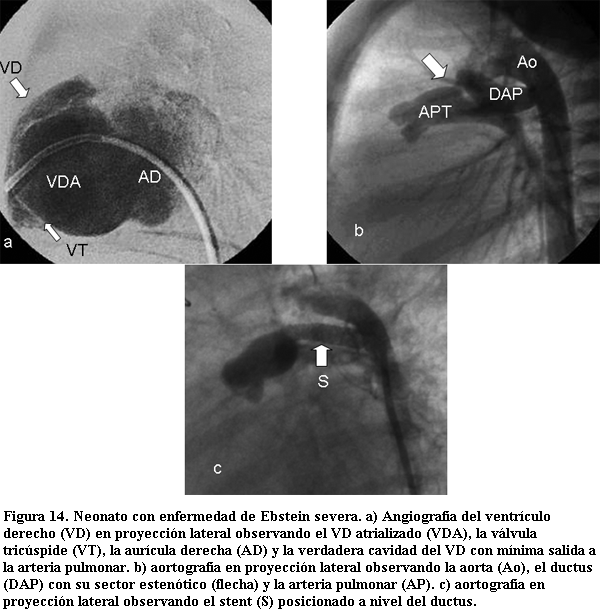

Valvulotomía pulmonar

Las cardiopatías congénitas con flujo pulmonar ductus dependiente y válvula pulmonar imperforada, se estabilizan mediante infusión de prostaglandinas y posteriormente requieren la realización de una fístula sistémico pulmonar (Blalock-Taussig) o la apertura de la válvula pulmonar mediante perforación por radiofrecuencia y posterior dilatación con catéter balón. Dependiendo de las características del VD este procedimiento puede ser suficiente, o en casos de un ventrículo muy hipertrofiado o con una clara restricción diastólica, la sola apertura de la válvula pulmonar puede ser insuficiente y continuar comportándose como ductus dependiente; en estos casos se puede optar por una conducta expectante bajo infusión de prostaglandinas en espera de que ese ventrículo adquiera una capacidad diastólica adecuada, mantener permeable el ductus mediante el implante de un stent o realizar una fístula sistémico pulmonar (2-6).

La dilatación de estas lesiones con catéter balón implica un éxito del 50%, el cual se incrementa a más del 90% con el uso combinado de stents, dentro de los cuales cobran importancia los stents flexibles (Génesis) que se adaptan mejor al árbol arterial pulmonar y los stents recubiertos en caso de lesiones nativas, o tras el uso de un cutting balón (figuras 12, 13 y 14) (74).